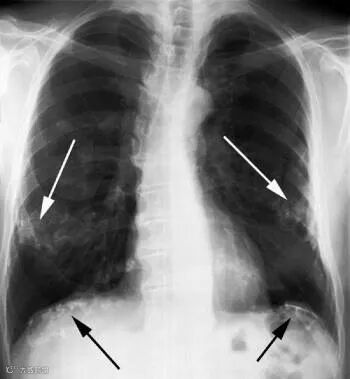

具体而言,急性二氧化硫中毒可引起眼、鼻、黏膜刺激症状,严重时产生喉头痉挛、喉头水肿、支气管痉挛;一旦大量进入人体,更可能引起肺水肿、窒息、昏迷,甚至导致死亡。

而长期小剂量接触二氧化硫可造成慢性中毒,最终会导致嗅觉迟钝、慢性鼻炎、支气管炎、肺通气功能和免疫功能下降;严重者可引起肺部弥漫性间质纤维化和中毒性肺硬变。